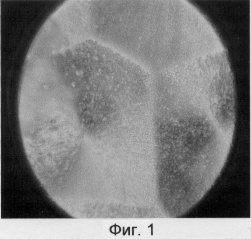

Пример 1. На поверхность стеклянной пластины наносят тонкий слой полианилина, на поверхности которого при выдерживании в течение 2 минут в 0,03% водном растворе сыворотки, приготовленной к вирусу гриппа типа В, иммобилизуют антитела к вирусу гриппа типа В (гомологичная система). После этого пластину 2 минуты промывают водой и подвергают обработке вирусом типа В в 0.15 М растворе NaCl в течение 2 минут, а затем 5 минут промывают водой и высушивают на воздухе 10 минут. Затем на нее наносят декорирующий ( 1 мкм) слой нематического жидкого кристалла метоксибензилиденбутиланилина (МББА) в виде раствора в этиловом спирте (или другом летучем растворителе) и помещают в поле зрения поляризационного микроскопа. После испарения растворителя область локализации комплексов антиген-антитело выглядит как характерная структура, показанная на Фиг.1 (диаметр поля наблюдения 800 нм). Видно, что в этом случае на поверхности образца формируются упорядоченные подобные твердым кристаллам структуры с осью симметрии 6-го порядка. Длительность проведения анализа не превышает 30 мин.